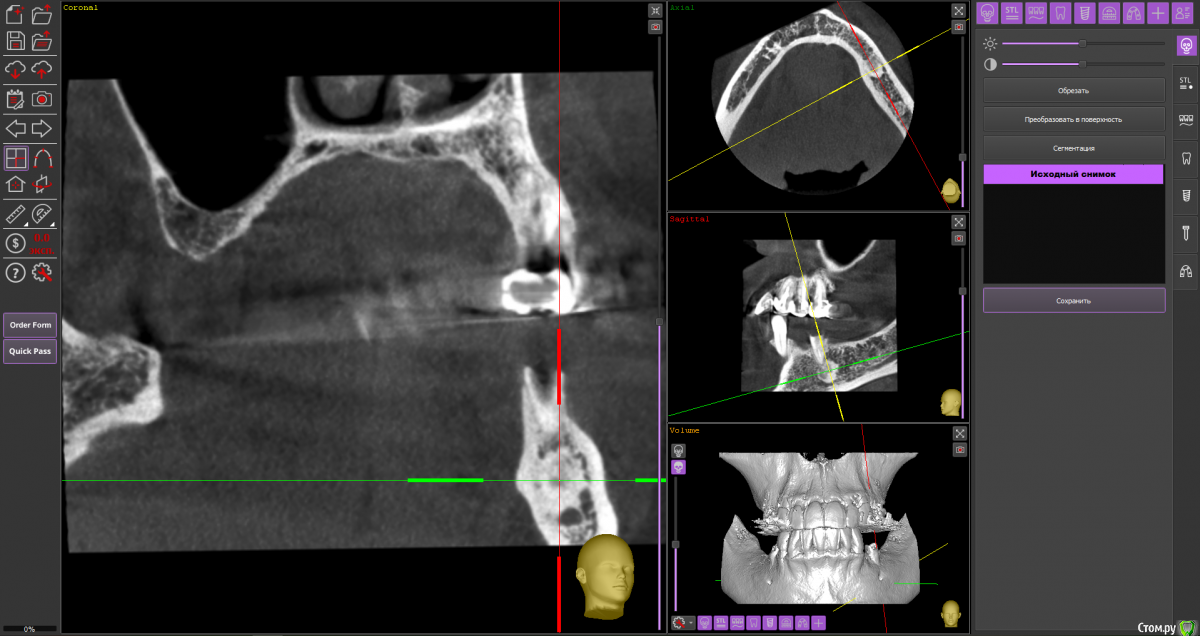

Fin Опубликовано 6 мая, 2020 Поделиться Опубликовано 6 мая, 2020 Здравствуйте коллеги. Пришла пациентка, для установки импланта в обл 3.6. После осмотра КТ обнаружил образование в проекции будущего импланта. В ходе осмотра КТ так же обнаружилось несколько подобных образований по НЧ. Помогите советом, кто сталкивался с подобной ситуацией и что это может быть? Ссылка на комментарий

Дмитрий Л. Опубликовано 6 мая, 2020 Поделиться Опубликовано 6 мая, 2020 Ну сделайте трепан биопсию. Через пару недель можно будет и имплант вкрутить. Я думаю что это костный рисунок. Ссылка на комментарий

wladdX Опубликовано 6 мая, 2020 Поделиться Опубликовано 6 мая, 2020 (изменено) Мне тоже кажется, что вы принимаете балочную структуру и петли н\ч канала за н\образование. Такое встречается иногда. Похожий случай На ОПТГ выглядит уже не так трагично Изменено 6 мая, 2020 пользователем wladdX 1 Ссылка на комментарий

It'sGeorgy Опубликовано 6 мая, 2020 Поделиться Опубликовано 6 мая, 2020 Тоже часто сталкиваюсь с таким. Костный рисунок. 1 Ссылка на комментарий

Fin Опубликовано 7 мая, 2020 Автор Поделиться Опубликовано 7 мая, 2020 Мне тоже кажется, что вы принимаете балочную структуру и петли н\ч канала за н\образование. Такое встречается иногда. Похожий случай46_1.jpg На ОПТГ выглядит уже не так трагичноОПТГ фрагмент.jpgЧестно говоря тоже думаю, что костный рисунок но смутили размеры и то что в других местах кроме этих таких явлений не наблюдается. Сейчас пациент предоставил снимок до ортод. лечения. На нем немного видно костный рисунок. Ссылка на комментарий

Fin Опубликовано 7 мая, 2020 Автор Поделиться Опубликовано 7 мая, 2020 Тоже часто сталкиваюсь с таким. Костный рисунок.Извините, хотел нажать кнопку ответа а поставил минус((.Такое тоже вижу очень часто, но смущают размеры. Ссылка на комментарий